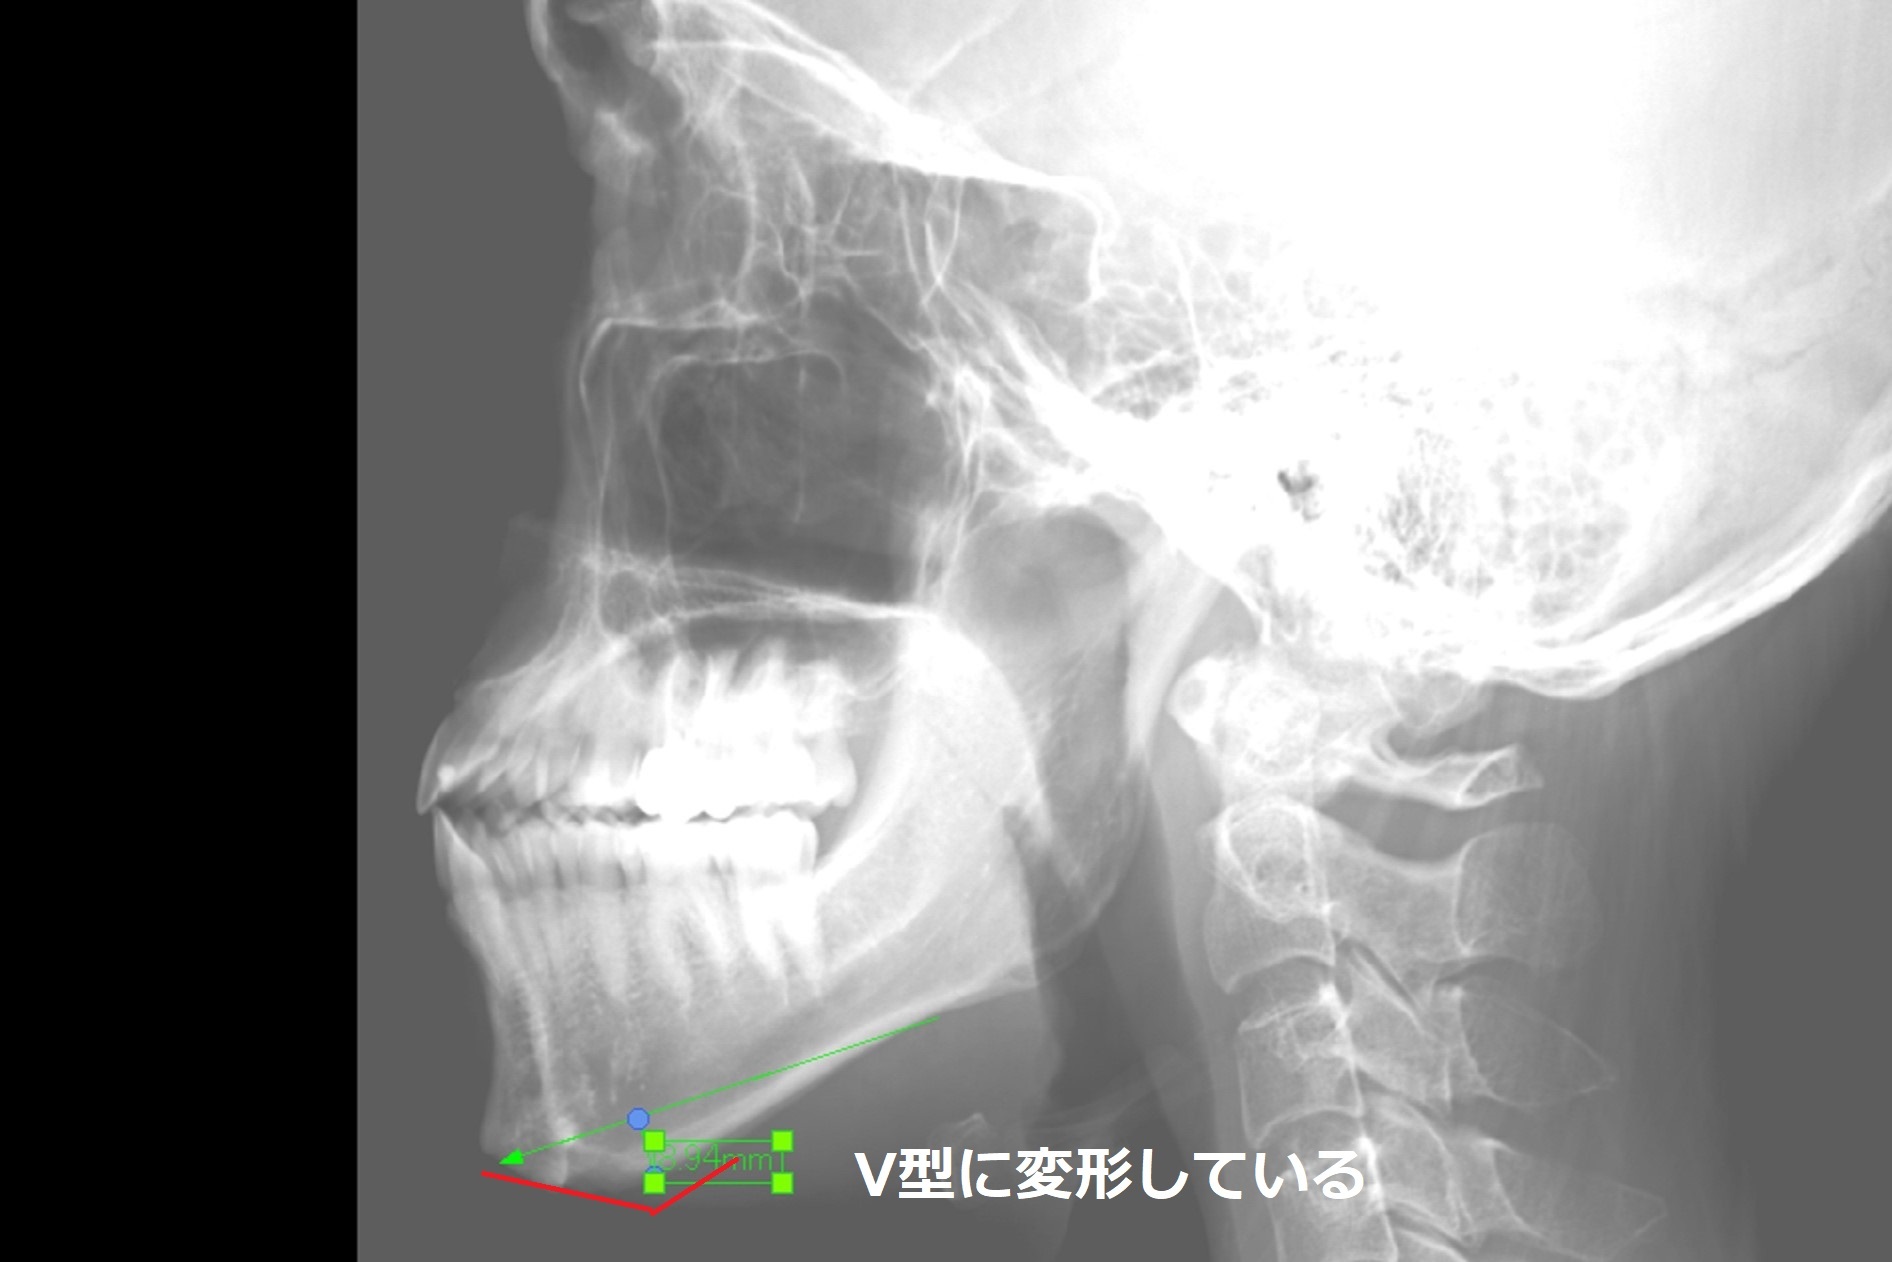

レントゲン写真上も 顎先を水平に削っていますが、側面像では、V型の骨の出っ張りが残っています。